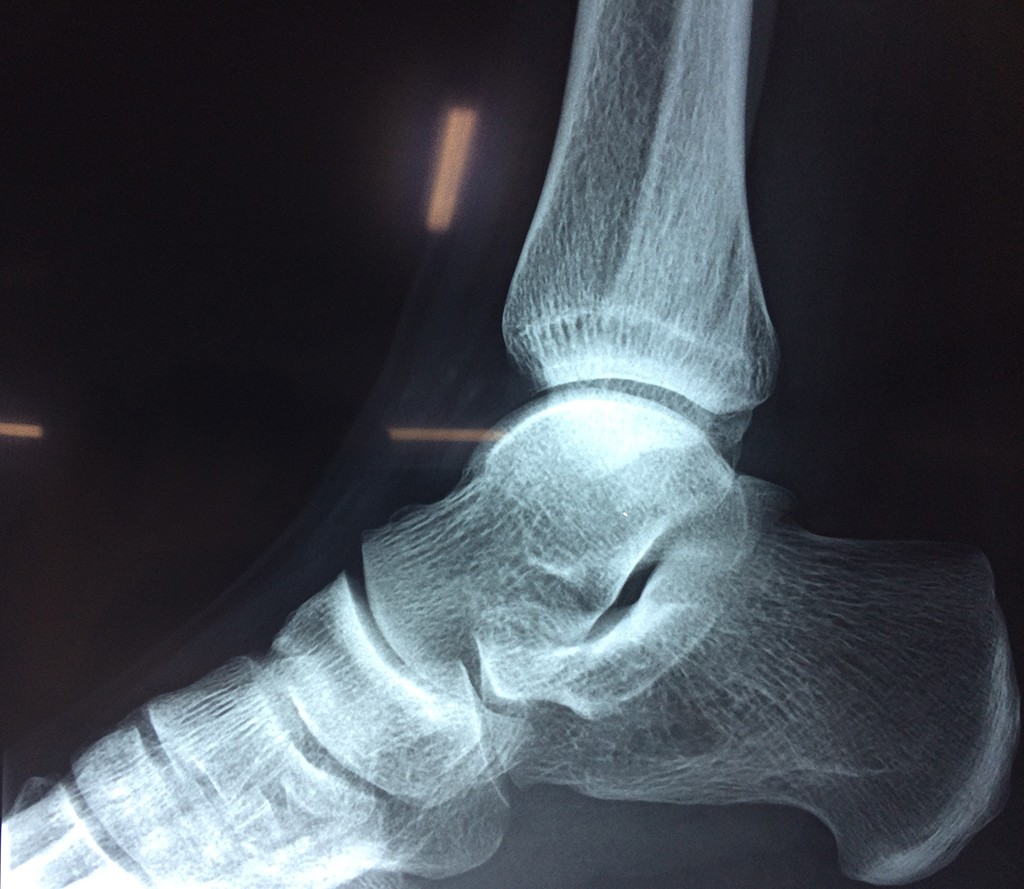

Una fractura de tobillo es la rotura de uno o más de los huesos del tobillo. Estas fracturas pueden ser:

- Parciales (el hueso está sólo parcialmente fisurado, no del todo).

- Completas (el hueso está perforado y está en 2 partes).

- Producirse en uno o ambos lados del tobillo.